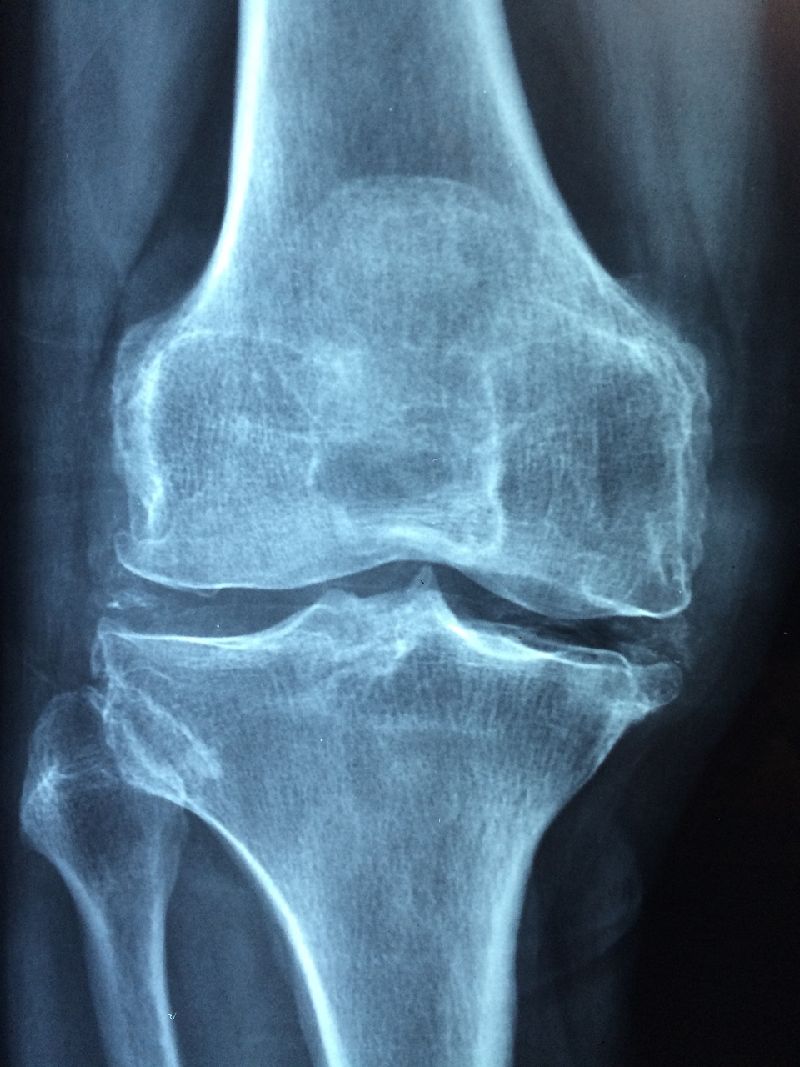

콘드로이친은 인체에서 자연적으로 발생하는 물질로, 주로 연골에서 많은 양이 발견됩니다. 콘드로이친은 관절 건강을 개선하고 관절염이나 관절 통증을 예방하는 효과가 있지만, 나이가 들수록 체내 함량이 감소하는 단점을 가지고 있습니다.

2.3 연골 보호

콘드로이친은 연골을 구성하는 성분으로, 연골을 더 튼튼하게 만들고 보호하는 역할을 합니다. 연골에 대한 더 자세한 내용은 [여기]를 참고하시기 바랍니다. 한 연구에 따르면 콘드로이친을 복용한 환자들은 연골의 손실이 33% 감소했고, 연골의 밀도가 5.4% 증가했습니다.